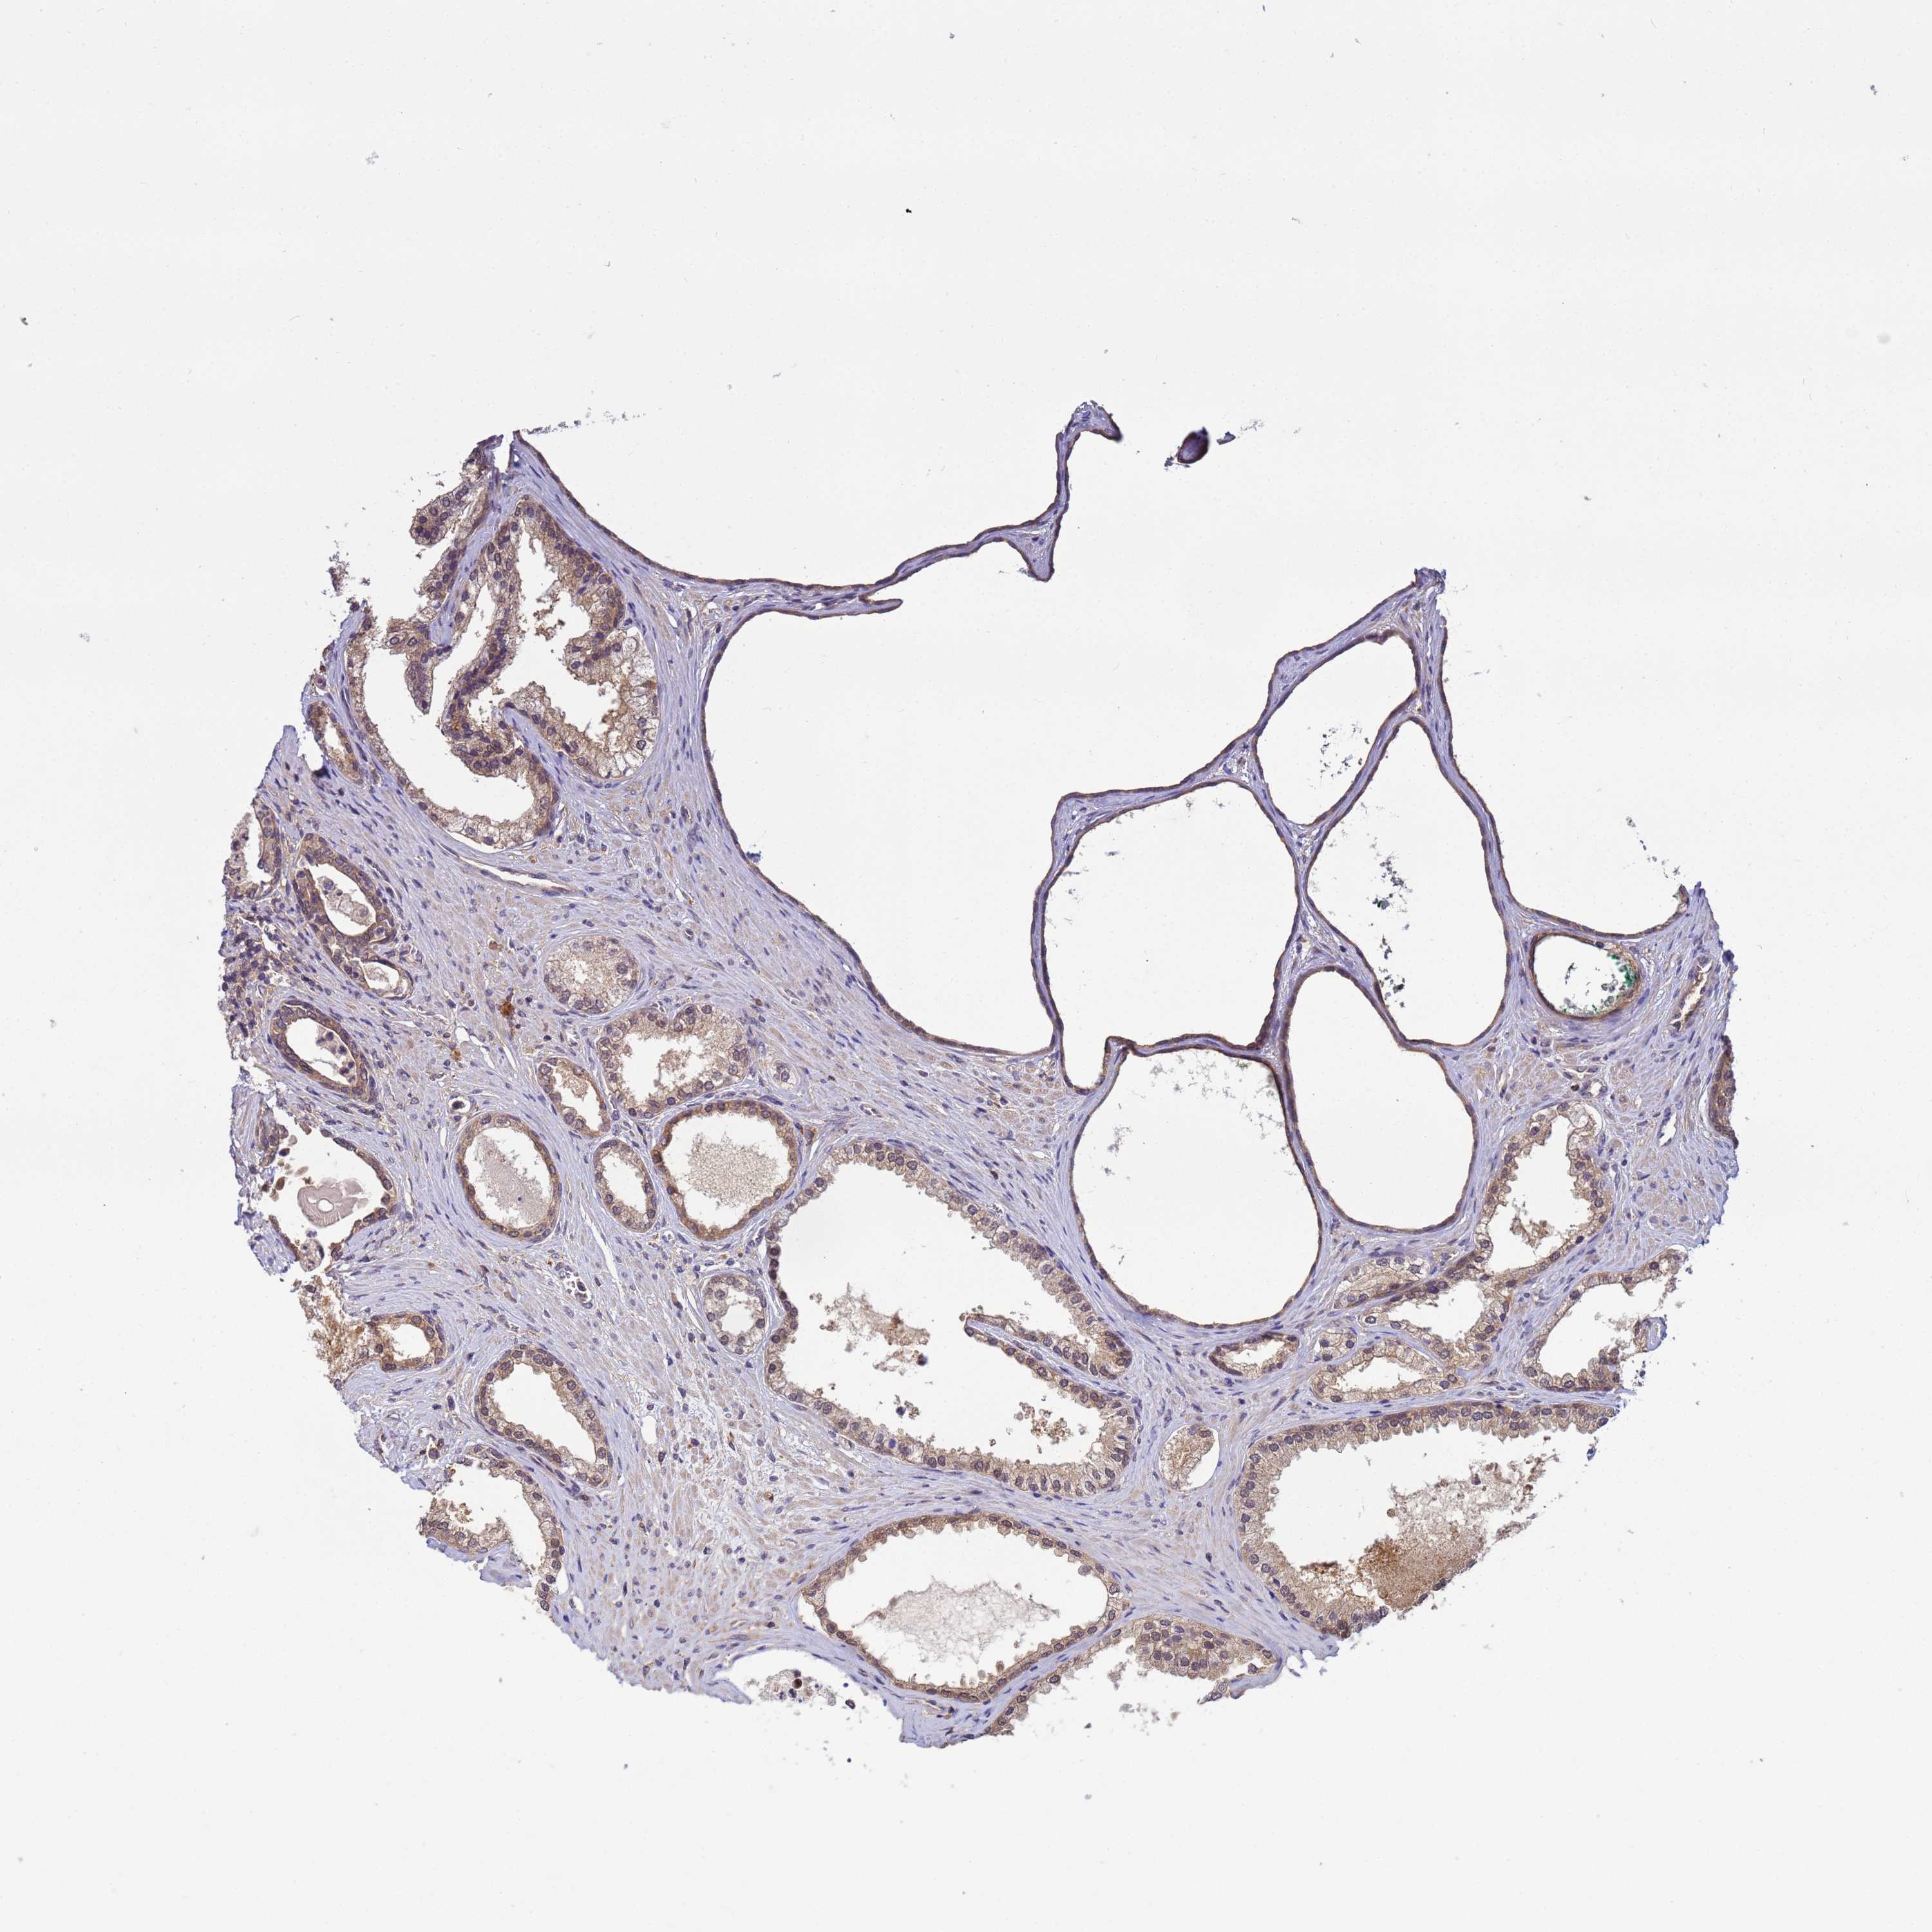

PROSTATE CANCER - Protein expressioni

A mouse-over function shows sample information and annotation data. Click on an image to view it in a full screen mode. Samples can be filtered based on level of antibody staining by selecting one or several of the following categories: high, medium, low and not detected. The assay and annotation is described here.

Note that samples used for immunohistochemistry by the Human Protein Atlas do not correspond to samples in the TCGA dataset.

Antibody stainingi

Antibody staining in the annotated cell types in the current human tissue is reported as not detected, low, medium, or high, based on conventional immunohistochemistry profiling in selected tissues. This score is based on the combination of the staining intensity and fraction of stained cells.

Each image is clickable and will lead to virtual microscopy that enables deeper exploration of all samples and also displays staining intensity scores, fraction scores and subcellular localization as well as patient and tissue information for each sample.

Antibody HPA021453

Antibody HPA045649

Staining

High

Medium

Low

Not detected

Intensity

Strong

Moderate

Weak

Negative

Quantity

>75%

75%-25%

<25%

None

Location

Nuclear

Cytoplasmic/membranous

Cytoplasmic/membranous,nuclear

Adenocarcinoma, NOS

Adenocarcinoma, High grade

Adenocarcinoma, Low grade